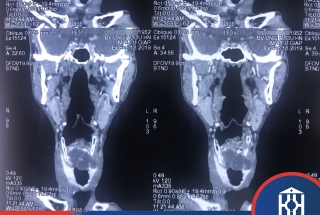

MỞ KHÍ QUẢN TƯ THẾ NẰM NGHIÊNG CHO BỆNH NHÂN U KHÍ QUẢN HIẾM GẶP

Các bác sĩ khoa Ngoại Đầu cổ - Bệnh viện Ung Bướu Hà Nội vừa phẫu thuật thành công, mở khí quản ở tư thế nằm nghiêng, cắt bỏ khối u khí phế quản trên cổ của một bệnh nhân 67 tuổi. Đây được xem là trường hợp rất hiếm gặp ở người cao tuổi. Hơn nữa, u khí phế quản thường nằm trong lồng ngực, nhưng bệnh nhân này u lại phát triển tại cổ gây khó thở dữ dội tăng dần, nguy cơ tử vong.